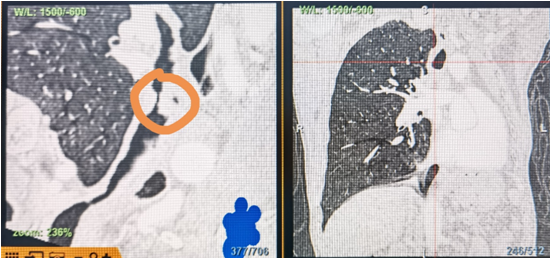

時(shí)間就是生命!了解患者病情后,歐陽海峰立刻啟動(dòng)氣道梗阻緊急救治通道,協(xié)調(diào)院前轉(zhuǎn)運(yùn),急診快速入院流程。凌晨患者入院胸部CT顯示,現(xiàn)存唯一的呼吸通道在右主支氣管處,狹窄處僅約3毫米,患者命懸一線!

運(yùn)用呼吸介入技術(shù),軟硬鏡結(jié)合快速開通氣道,是患者目前唯一可行的治療方案,手術(shù)刻不容緩!但存在麻醉后氣道完全塌陷閉合、大出血、窒息等巨大風(fēng)險(xiǎn)?;颊叽饲敖舆B轉(zhuǎn)診3家醫(yī)院,均建議保守支持治療或轉(zhuǎn)院。歐陽海峰詳細(xì)了解患者病史,全面評(píng)估影像檢查結(jié)果后,決定盡快進(jìn)行手術(shù),組織醫(yī)護(hù)團(tuán)隊(duì)對(duì)患者進(jìn)行持續(xù)密切監(jiān)測(cè),充分保障其術(shù)前安全。

患者入院第二天,在麻醉手術(shù)中心全力配合下,歐陽海峰帶領(lǐng)呼吸介入團(tuán)隊(duì),歷時(shí)40分鐘快速置入硬質(zhì)支氣管鏡、鏟切腫瘤,并順利植入全覆膜TTS支氣管金屬支架?;颊邭舛贪Y狀即刻緩解,為患者贏得了寶貴的后續(xù)治療機(jī)會(huì)。